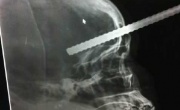

استشهاد فتاة متأثرة بإصابة في رأسها في الدية

2011-12-07

مرآة البحرين: استشهدت الفتاة زهراء صالح (27 عاماً)، الأربعاء، متأثرة بإصابتها في الرأس أثناء وجودها في منطقة الدية الشهر الماضي.